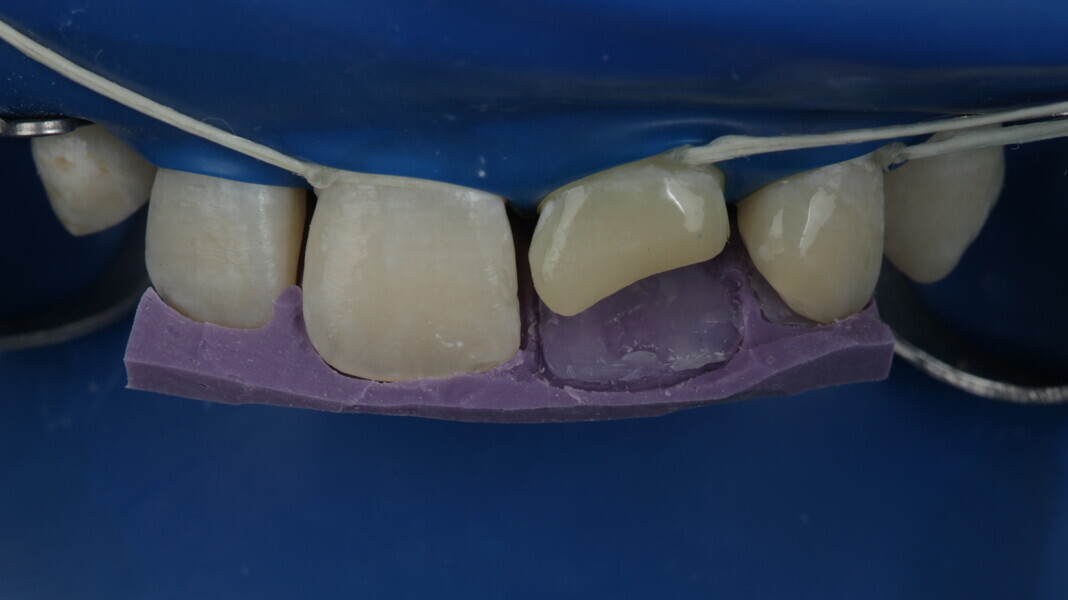

Fig 25-30: Layering protocol step by step